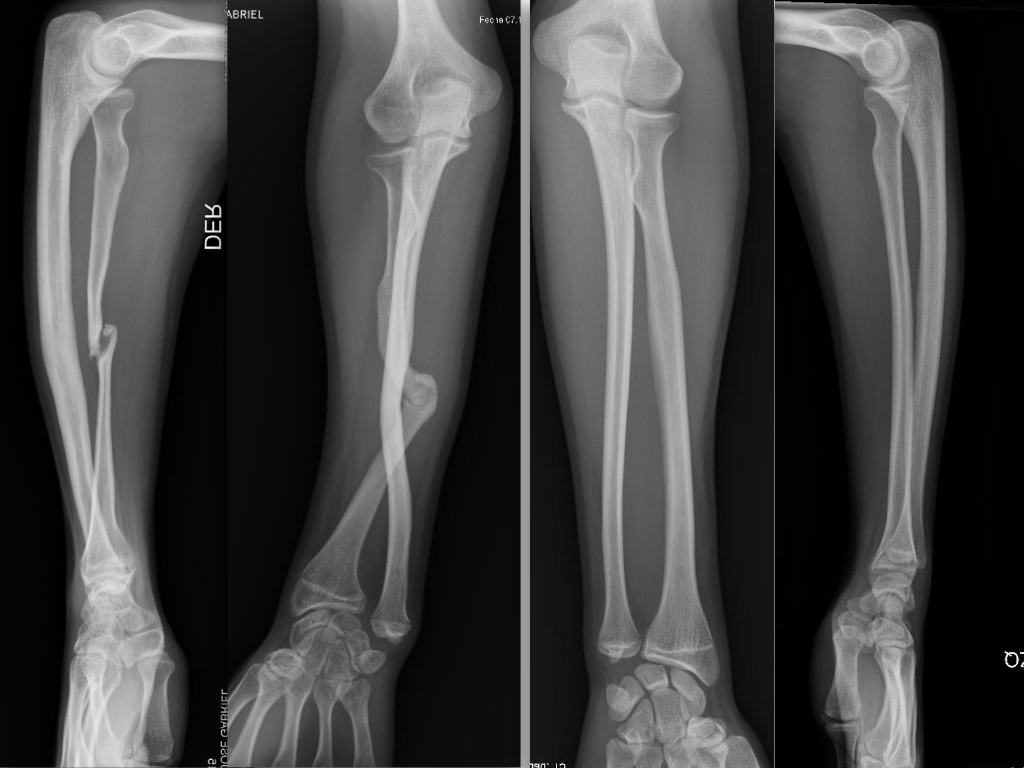

Introducción Los defectos óseos mayores a 6 cm en los huesos largos resultan en un problema difícil a reconstruir del miembro superior. Entre las opciones se encuentran: el injerto óseo alogénico, la utilización de la técnica de Masquelet y el injerto vascularizado de peroné. El peroné vascularizado se ha convertido en el principal método de reconstrucción por sus ventajas biológicas. El objetivo del presente estudio fue evaluar la tasa y el tiempo de consolidación ósea y las complicaciones asociadas en una serie continua de pacientes. Material y MétodosSe realizó una revisión del registro para identificar a todos los pacientes que se sometieron a una reconstrucción con peroné vascularizado durante un periodo de 5 años. Se incluyeron a todos los pacientes que fueron tratados por defectos mayores de 6cm en miembro superior y se excluyeron aquellos en que la reconstrucción se llevó a cabo en el miembro inferior o como técnica asociada para aumentación de la estabilidad en artrodesis de hombro. Se analizaron variables preoperatorias, intraoperatorias y postoperatorias inmediatas y alejadas. Resultados Durante el periodo de evaluación, 18 pacientes fueron sometidos a cirugías reconstructivas con IVP. Seis pacientes (4 hombres/2 mujeres) cumplían con los criterios de inclusión. La edad promedio fue de 47 años (rango 16 a 66 años). En promedio, los pacientes tenían 3 cirugías previas (rango 1 a 4). El tiempo transcurrido entre el trauma inicial y la cirugía reconstructiva varió de 2 a 21 años (promedio 7 años). Las causas del defecto fueron la secuela postraumática (pseudoartrosis) en cinco pacientes y la enfermedad oncológica en un paciente con diagnóstico de Tumor de Células Gigantes. Los segmentos óseos involucrados fueron el húmero (tres pacientes), radio (dos), y cubito (uno). El defecto óseo promedio fue de 10 cm (rango 6 a 15 cm). En cuatro casos se utilizó un injerto osteocutáneo de peroné y un caso sin colgajo fasciocutáneo asociado. En todos los casos, se utilizaron placas bloqueadas como método de fijación del injerto. El tiempo de seguimiento promedio fue de 17 meses (rango de 5 a 40 meses). La consolidación ósea fue lograda en todos los casos. La consolidación ósea llevó promedio de consolidación ósea fue de 16 semanas (rango de 8 a 22 semanas). Dos pacientes sufrieron complicaciones posoperatorias. Un paciente sufrió una exposición del material de osteosíntesis. Otro paciente evolucionó con aflojamiento del material de osteosíntesis. Ninguno de los pacientes presentó complicaciones o secuelas funcionales en la zona dadora. Conclusión El injerto óseo vascularizado de peroné es una opción válida para el tratamiento quirúrgico reconstructivo de defectos óseos segmentarios mayores a 6cm en el miembro superior con una tasa alta de consolidación, aún en casos con múltiples cirugías previas o con larga evolución de la lesión. Los detalles técnicos previenen las complicaciones en la zona dadora.Descargas